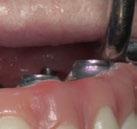

Figura 3. Visión intraoral oclusal mandibular. Figura 4. Visión intraoral frontal. Figura 1. Visión intraoral oclusal maxilar. Figura 2. Visión lateral izquierda intraoral. Figura 7. Escaneado intraoral maxilar con Dexis IS3700. Figura 8. Escaneado intraoral mandibular con Dexis IS3700. Figura 5. Visión extraoral lateral sonrisa.